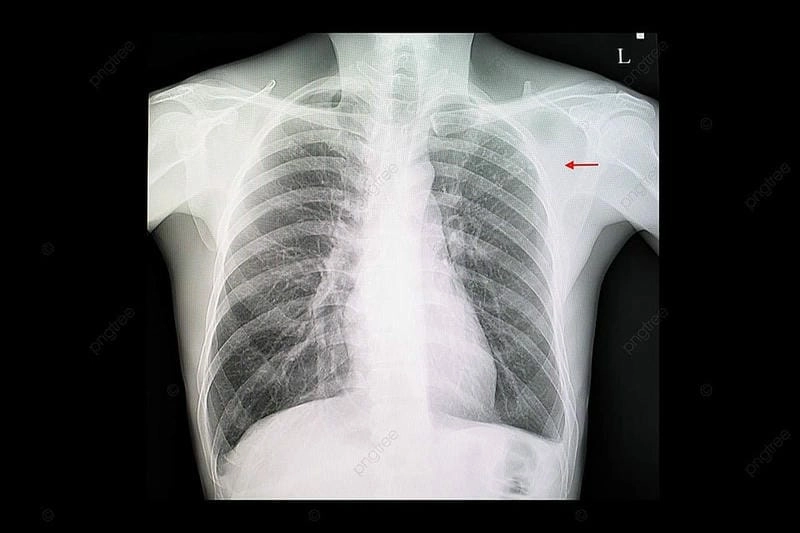

Hình ảnh bệnh lao phổi là tài liệu tham khảo quan trọng giúp người bệnh và bác sĩ dễ dàng nhận biết dấu hiệu bất thường. Việc quan sát hình ảnh X-quang, CT phổi giúp chẩn đoán chính xác mức độ tổn thương và đưa ra phương án điều trị kịp thời.

Bạn sẽ phải rùng mình khi chiêm ngưỡng hình ảnh bệnh lao phổi là như thế nào dưới ống kính y học thực tế. Những bức ảnh chụp X-quang cho thấy phổi bị tổn thương nặng, xuất hiện những đốm trắng mờ như bóng ma ám ảnh. Không chỉ là các tổn thương vật lý, đây còn là những “chứng tích sống” của căn bệnh âm thầm hủy hoại cơ thể qua từng hơi thở. Từ viêm nhẹ đến tổn thương lan rộng, hình ảnh bệnh lao phổi khiến người xem không thể rời mắt vì mức độ nghiêm trọng mà nó thể hiện rõ ràng qua từng chi tiết.

Cảnh báo: tổng hợp ảnh bệnh lao phổi chân thực này không dành cho người yếu tim. Đây là loạt hình ảnh y khoa được các chuyên gia sưu tầm và xác thực, ghi lại quá trình tiến triển của bệnh từ giai đoạn đầu đến giai đoạn nguy kịch. Từng mảng mô phổi bị ăn mòn, xơ hóa, hoại tử được phơi bày rõ nét dưới ánh sáng X-quang lạnh lùng. Những hình ảnh này không chỉ mang tính chất minh họa y học, mà còn là hồi chuông cảnh tỉnh cho bất kỳ ai còn lơ là với căn bệnh nguy hiểm này.